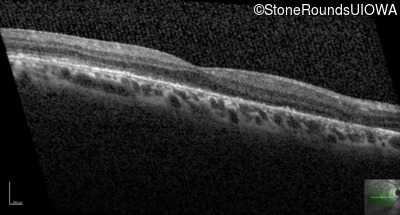

Foveal Hypoplasia (IIIG)

Diagnosis & molecular findings

Disease Gene Allele 1 variant(s) Allele 2 variant(s) Inheritance mode

Foveal Hypoplasia PAX6 Pro76Leu CCG>CTG   AD